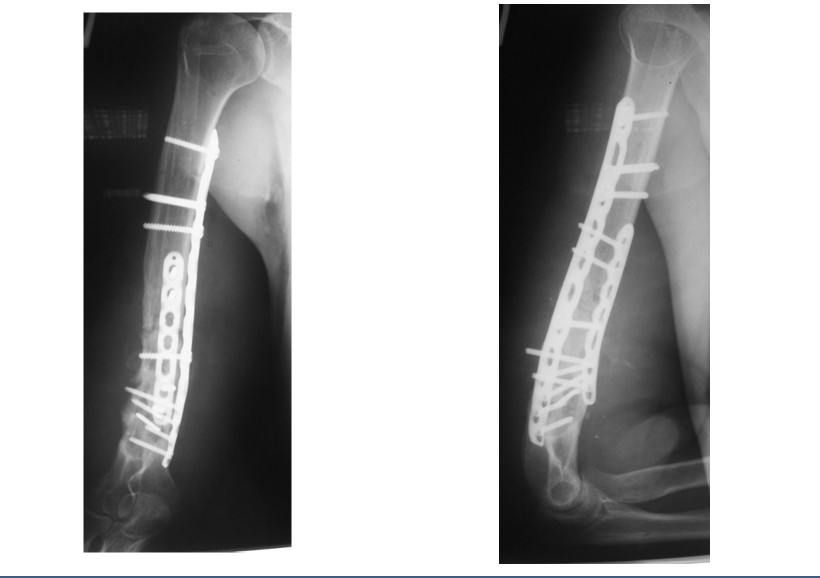

Этап 2: пластика несращения свободным реваскуляризированным костным трансплантатом из медиального мыщелка бедра, фиксация трансплантата пластиной.

Подключение костного лоскута к кровотоку с помощью микрохирургической техники

Рентгенограммы после операции по васкуляризированной костной пластике